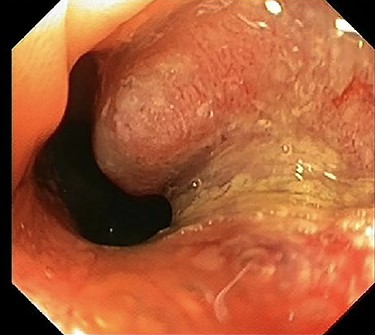

One year after surgery, his right testis was swollen and painful. There was no dysuria or hematuria. On scrotal examination, a small nodule (approximately 1 cm in diameter) was felt in his right testis. Ultrasonography showed a hydrocele of the right testis with thickening of the scrotal wall and a tumorous mass (Fig. 4). An orchiectomy was performed and pathologic analyses revealed a metastasis of the adenocarcinoma between tunica albuginea and tunica vaginalis. He started palliative chemotherapy containing capecitabine and bevacizumab. The CT scan after three cycles of chemotherapy showed a partial remission.

Ultrasonography of right testis showing hydrocele and a tumorous mass.